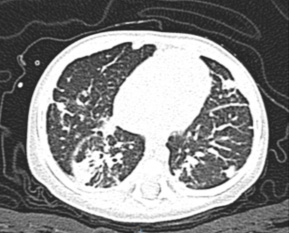

Se ha encontrado que las manifestaciones crónicas más frecuentes son anemia por infección crónica (65 %), linfadenopatía (52 %), hepatoesplenomegalia (25 %) y alteraciones gastrointestinales (25 %). A nivel pulmonar son más frecuentes bronquiectasias, bronquiolitis obliterativa y fibrosis crónica (figura 2). Por otra parte, las manifestaciones cutáneas incluyen fotosensibilidad, lesiones granulomatosas y vasculitis.6,23